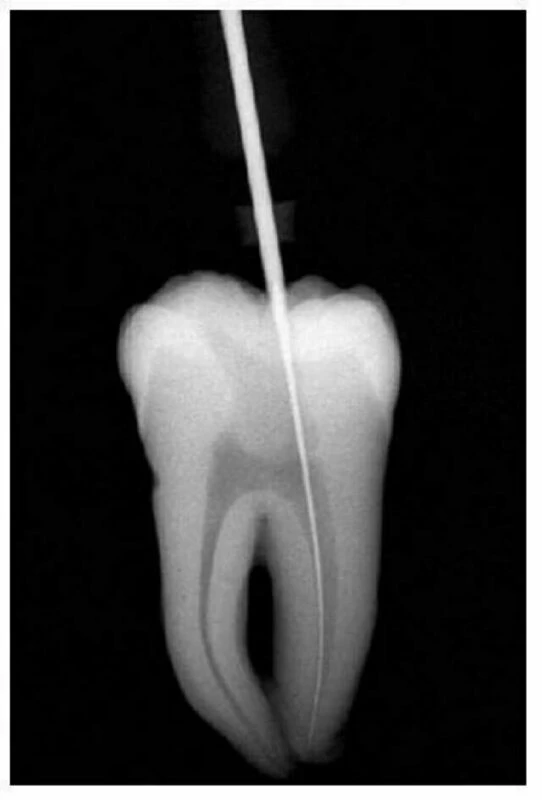

Hình 11.14. A. Phim trước điều trị R36: chân gần cong 1/3 trên. B. Mở đầu bằng trâm số #8 đi vào ống ngoài gần, nhận thấy ống tủy cong về phía xa và phía lưỡi. C. Xoang tủy được mở rộng về phía gần và phía má, phạm vào múi gần ngoài. D. Trâm số #20 có một đường vào thẳng đến 1/3 chóp của ống tủy.

Hình 3.15. A. Phim răng cối lớn 1 hàm trên, chân răng gần ngoài bị cắt vì lý do nha chu. B. Mở lối vào ống tủy, tháo đê cao su để clamp không gây trở ngại cho việc chụp phim kiểm tra lỗ vào ống tủy. C. Dùng file 06 ở chân xa ngoài sau khi chân trong đã được tìm thấy, làm sạch và tạo hình. Nên tháo đê cao su để tiện cho việc kiểm tra ống tủy. Cán dụng cụ nên buộc vào chỉ nha khoa và buộc đầu chỉ còn lại bên ngoài. D. Đặt lại đê cao su và hoàn thành việc điều trị theo cách truyền thống. E. Phim sau điều trị. F. Sau 4 năm.